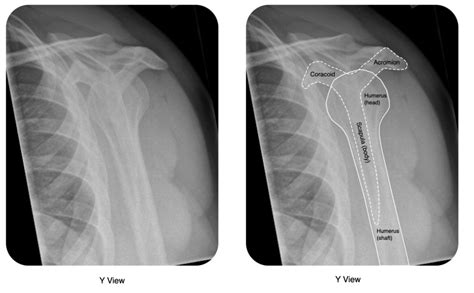

When it’s time for the X-ray, you’ll be guided into a special room that houses the X-ray machine. The technician will position you carefully, ensuring that your shoulder is in the correct position for the images. You might need to stand, sit, or lie down, depending on the specific views the doctor needs. The technician might place lead aprons or shields over parts of your body that don’t need to be X-rayed. These shields help to minimize radiation exposure. During the X-ray, you’ll need to stay as still as possible. Movement can blur the image, making it harder to read. The technician will step behind a protective barrier and activate the machine. You might hear a whirring or clicking sound – that’s perfectly normal. The X-ray itself takes only a fraction of a second. Usually, multiple views are taken from different angles to get a complete picture of the shoulder joint. So, the process might be repeated a few times.

The primary goal of an X-ray in this scenario is to confirm whether a dislocation has occurred. A normal shoulder joint will show the head of the humerus (the ball) sitting neatly within the glenoid fossa (the socket). When a dislocation is present, the head of the humerus will be displaced, meaning it has popped out of the socket. The X-ray will clearly show this displacement. There are different types of shoulder dislocations, most commonly anterior (where the humerus moves forward) and posterior (where the humerus moves backward). The X-ray will help identify the direction of the dislocation, which is important for guiding treatment. It’s like having a map that shows exactly where the ball has rolled off the track. This visual confirmation is crucial for accurate diagnosis and planning the reduction (putting the shoulder back in place).